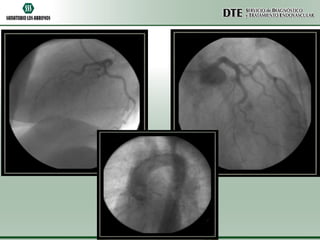

Cinecoronariografía

•Arteria descendente anterior de fino calibre y aspecto

hipoplásico.

•Arteria circunfleja y coronaria derecha sin lesiones

angiográficamente significativas.

•Acinesia de punta y segmentos apicales de pared anterior

e inferior.

•Moderado deterioro de la función sistólica ventricular

izquierda.